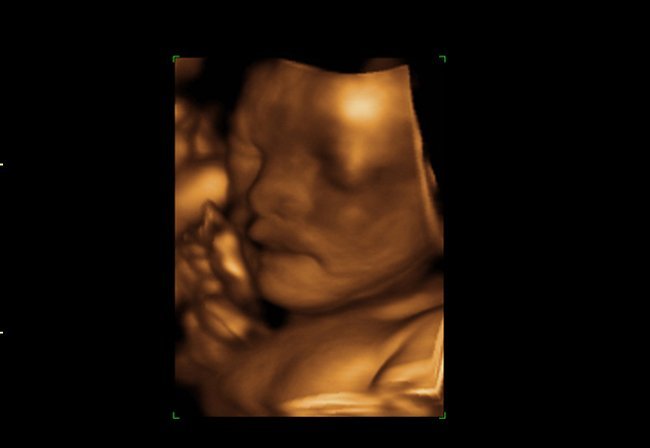

Los fetos bostezan en el vientre materno

Gracias a las últimas tecnologías conocemos que los bebés hacen el gesto de bostezar en el vientre materno, y un estudio científico ha querido aproximarse a este comportamiento para relacionarlo con la maduración del sistema nervioso central del feto.

El estudio, que analiza las secuencias de vídeo 4D de 15 fetos sanos (ocho femeninos y siete masculinos) de entre 24 a 36 semanas de gestación, distingue claramente el bostezo, del no bostezo o la boca abierta, centrándose an la duración de la apertura de la boca.

Los investigadores hallaron que más de la mitad de las aberturas de la boca observadas fueron bostezos, según publica la revista 'Plos One' en su último número. Otros datos son que el bostezo se redujo a partir de las 28 semanas y que no hubo diferencias significativas entre niños y niñas en la frecuencia del bostezo.

Ya que los bostezos disminuyen según la edad fetal, se trata de un indicador más de desarrollo del bebé. Y como a diferencia de nosotros, los fetos no bostezan por contagio ni por sueño, la frecuencia de los bostezos en el útero puede estar relacionada con la maduración temprana del cerebro en la gestación.